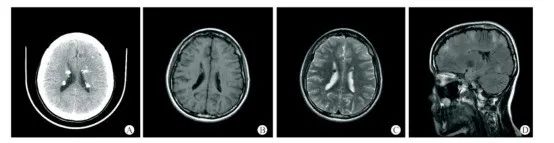

图6 19岁女性结节性硬化症患者的头颅CT+MRI平扫影像[6]

患者临床表现为癫痫及精神发育异常,右面部色素沉积斑、四肢及躯干多发色素脱失斑、双侧峡部皮脂腺瘤,胸椎多发斑片状致密影。A-C:头颅CT+MRI平扫示双侧室管膜下及皮层下多发结节样钙化灶;D:T2FLAIR示大脑半球皮层及皮层下多发异常高信号影。